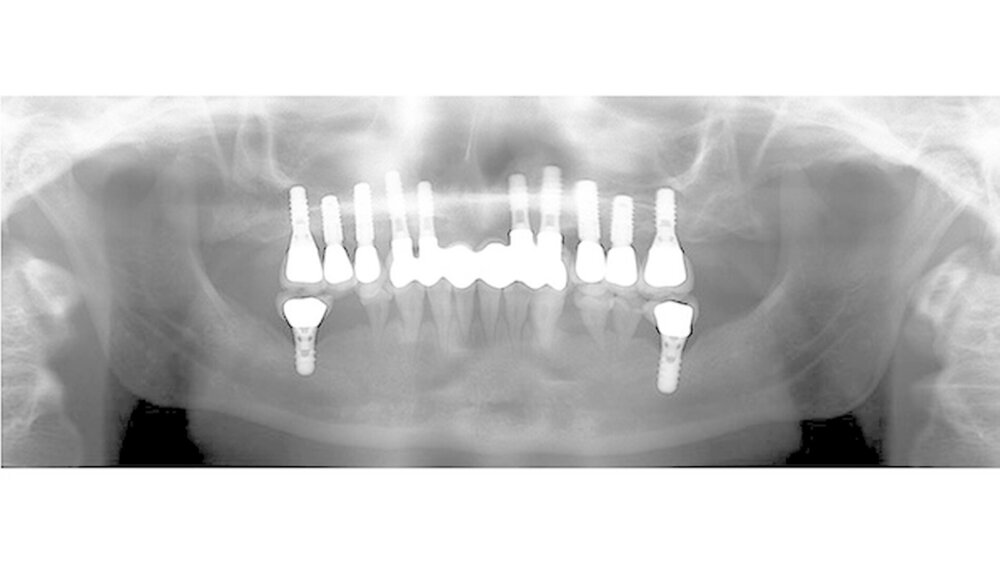

Daher mussten auch die Seitenzähne im Oberkiefer und teilweise im Unterkiefer entfernt und mit Implantaten ersetzt werden. Dies erfolgte unter anderem unter Einsatz von navigationsgestützten Techniken. Im Seitenzahnbereich des Oberkiefers musste eine Sinusaugmentation mit Knochen durchgeführt werden. Dabei wurde mit allen Vorsichtsmaßnahmen vorgegangen, die nach einer Bestrahlung des Knochens zu treffen sind.